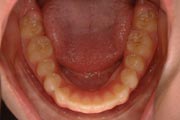

Crowding

After